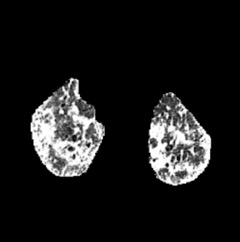

In the field of medical imaging, particularly in tasks related to early disease detection and prognosis, understanding the reasoning behind AI model predictions is imperative for assessing their reliability. Conventional explanation methods encounter challenges in identifying decisive features in medical image classifications, especially when discriminative features are subtle or not immediately evident. To address this limitation, we propose an agent model capable of generating counterfactual images that prompt different decisions when plugged into a black box model. By employing this agent model, we can uncover influential image patterns that impact the black model's final predictions. Through our methodology, we efficiently identify features that influence decisions of the deep black box. We validated our approach in the rigorous domain of medical prognosis tasks, showcasing its efficacy and potential to enhance the reliability of deep learning models in medical image classification compared to existing interpretation methods. The code will be publicly available at https://github.com/ayanglab/DiffExplainer.